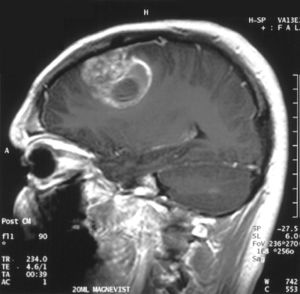

تصوير بالرنين المغناطيسي للمنطقة التاجية يظهر الورم الأرومي الدبقي في ذكر في الخامسة عشر من عمره. | |

- اختبارات التصوير: وغالبًا ما يستخدم التصوير بالرنين المغناطيسي للمساعدة في تشخيص أورام الدماغ. في بعض الحالات، قد يتم حقن صبغة (مواد تباين) خلال وريد في ذراع المريض أثناء دراسة التصوير بالرنين المغناطيسي للمساعدة في إظهار الاختلافات في أنسجة الدماغ.

قد يساعد عدد من مكونات التصوير بالرنين المغناطيسي المتخصصة — بما في ذلك التصوير بالرنين المغناطيسي الوظيفي، وتصوير التروية بالرنين المغناطيسي وتنظير الطيف بالرنين المغناطيسي — في تقييم الطبيب للورم وخطة العلاج.